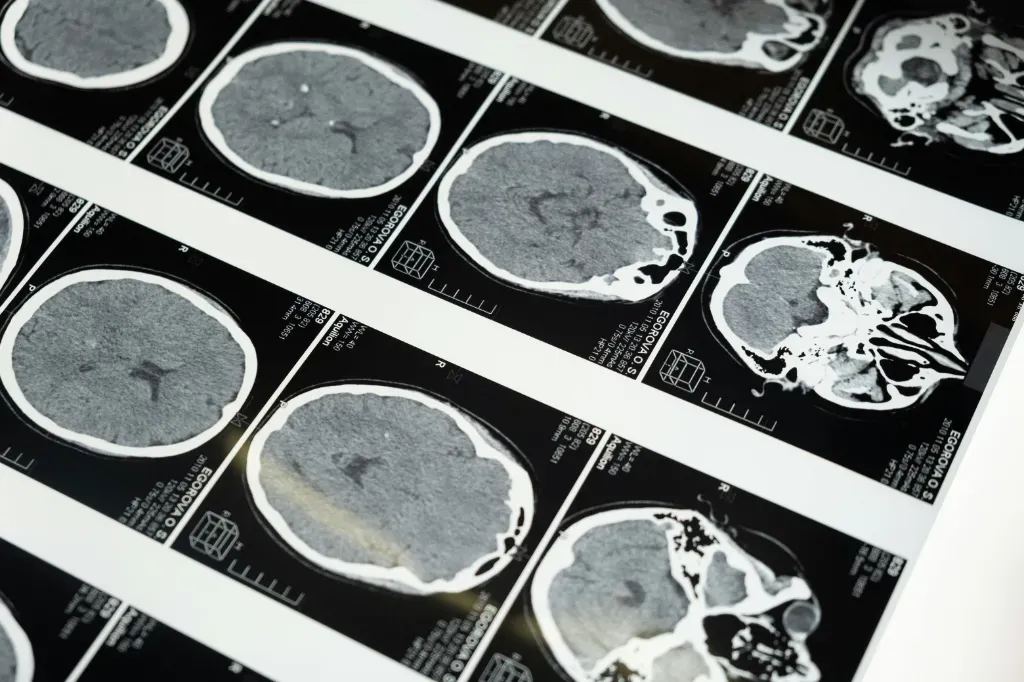

Najprościej mówiąc – to zdalny opis badań obrazowych. Szpital wykonuje tomografię, rezonans albo RTG, a system przesyła cyfrowe obrazy do radiologa w innym miejscu. Ten, korzystając z bezpiecznego oprogramowania, analizuje badanie i odsyła gotowy opis. W praktyce wygląda to tak, że pacjent z małego powiatowego szpitala może mieć dostęp do specjalisty na poziomie kliniki.

Najważniejszy powód to czas. Kiedy liczą się minuty – np. przy podejrzeniu udaru – szybki opis badania może zadecydować o życiu pacjenta. Zdalny model pozwala na dostęp do wyniku w trybie pilnym, i to nawet w nocy czy w święto. W tradycyjnym systemie pacjent musiałby poczekać, bo radiologa na miejscu po prostu nie było.